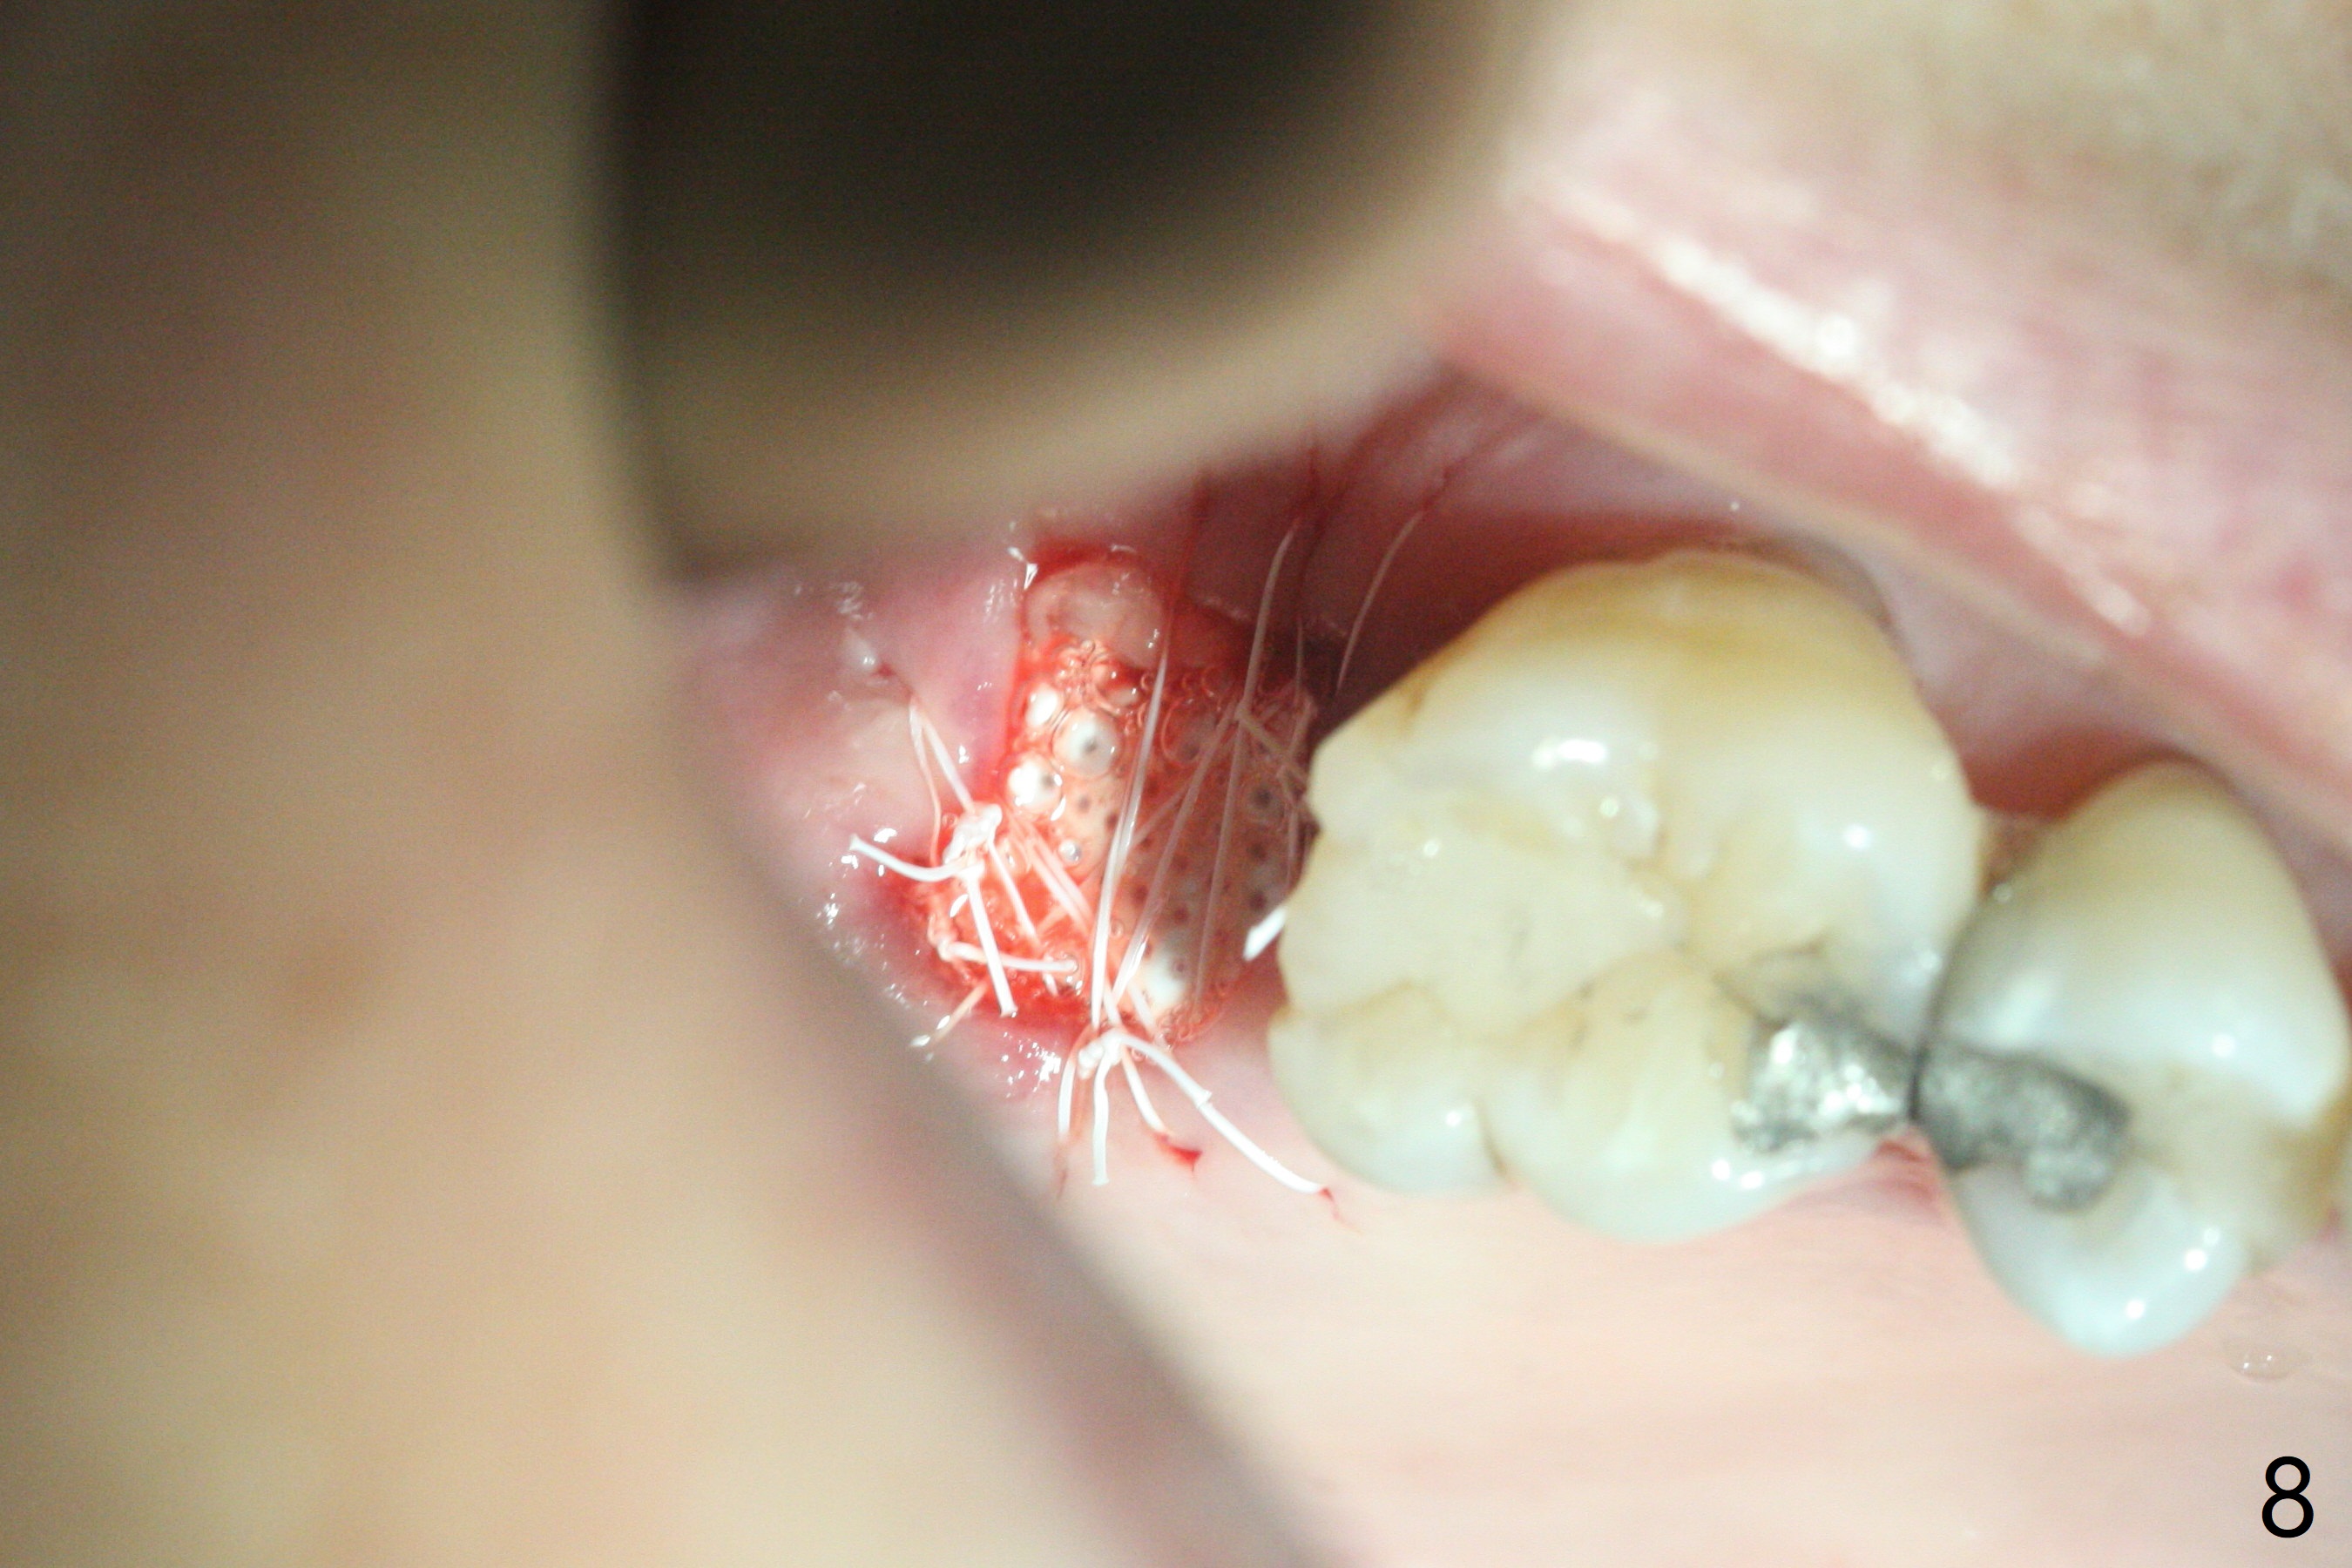

第二磨牙位点保留后,牙周敷料容易脱落,尤其上颌,本文介绍一种方法增加固位。右上七严重牙髓牙周综合征,拔出后使用刮匙除去骨面肉芽组织,颊侧骨板缺失,附着在颊侧粘骨膜上的肉芽组织使用一种叫Stieglitz angled, diamond splinter forceps (德国产,图一,二)撕下来。彻底清除炎性组织必须多次刮治,之间塞入带有灭滴灵(图三:粉剂)和1比50,000肾上腺素局麻药纱布(图四)止血,取出纱布,牙槽窝视野好,继续去除残余的肉芽组织。牙槽窝底部穿孔,用无齿刮匙稍微扩大穿孔后,使用图五下面小的骨粉输送器,将少量骨粉(粘性)送到穿孔处,推入上颌窦(图七:S),之后使用大的骨粉输送器(图五上面),把大量骨粉送到牙槽窝,使用图六上面大的,长的充填器,压实骨粉(图七),骨粉表面放置PRF膜和不可吸收膜(图八),在第一磨牙时安置粘固一个间隙维持器(图九,十),最后铺上牙周敷料(图十一),检查咬合空间,没有干扰。There are sign and symptom of sinusitis 1 week postop; large amount of bone graft retains in the socket by the periodontal dressing and spacer (Fig.12). The sinus membrane (Fig.7 immediate postop) thickens 1 week postop (Fig.13). Augmentin and Medrol Dose Pak are prescribed. 上颌窦炎一周后消失,腭侧牙周敷料丢失,伤口好像正常愈合(图十四)。术后三周牙周敷料由于大量水枪冲洗脱落(图十五)。因为病人需要离城两个月,间隙保持器撤除(图十六),不可吸收膜腭侧稍微外翻 (<),可能有利于术后五周自行脱落。No Deviation SP 下一个病例 位点保留后Xin 导板与张口度 第一磨牙即种 Wei, DDS, PhD, MS 1st edition 09/17/2020, last revision 04/30/2021